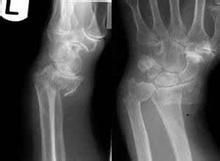

傷後腕部疼痛並迅速腫脹,出現與Colles骨折相反的畸形。腕關節主被動活動均因疼痛而受限,該部位有明顯壓痛及異常活動,尺橈骨莖突關係異常。 腕關節正側位X片光可以明確顯現骨折特點,可藉以診斷和分型。